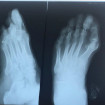

• Хирургическое лечение врожденных

и приобретенных патологий кисти и стопы.